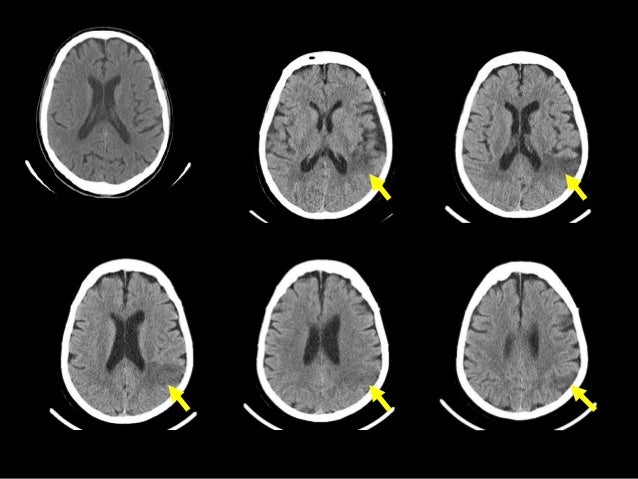

Cat Scan Images Of Brain